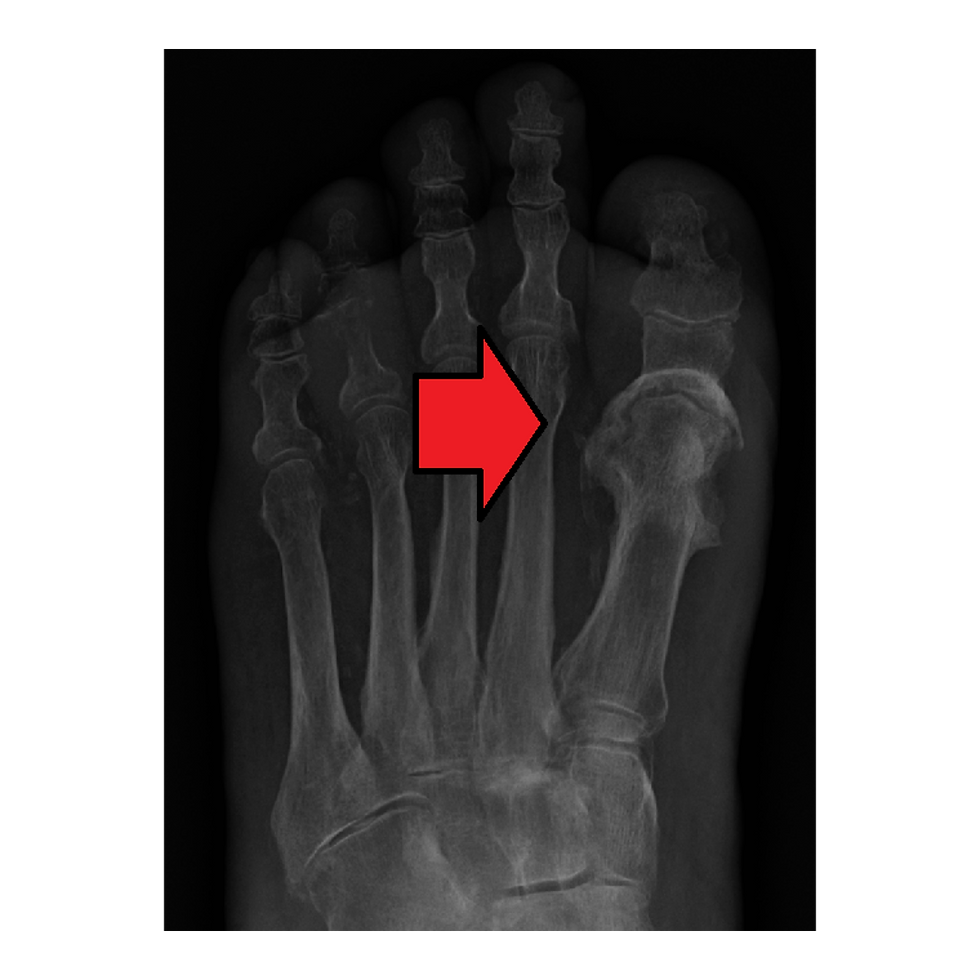

Zonas de hiperpressão, como cabeças metatarsianas e calcâneo, costumam ser locais favoráveis para a instalação do processo séptico. Não raro, a infecção atinge os compartimentos profundos do pé, aumentando bastante as chances de amputação do membro. Outras vezes, associa-se a quadros clínicos mais dramáticos, ameaçando bastante a manutenção, não só da extremidade, mas da vida do indivíduo.